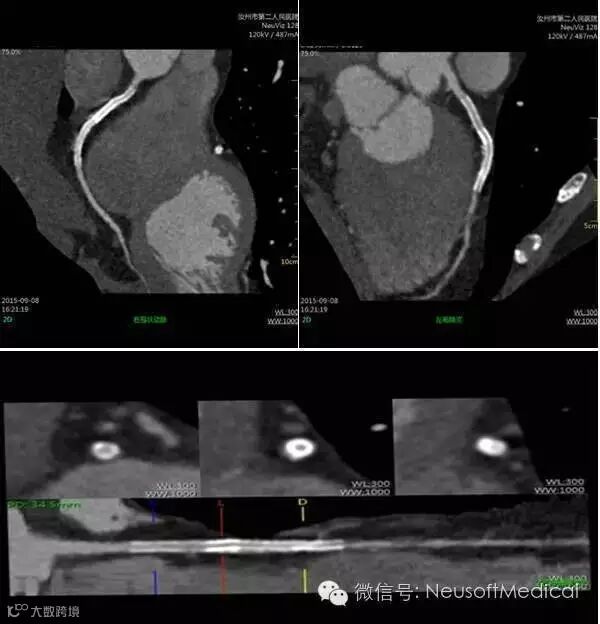

左:主动脉狭窄 右:左侧冠状动脉多发钙化斑

右冠状动脉金属支架置入术后复查,支架内管腔显示清晰